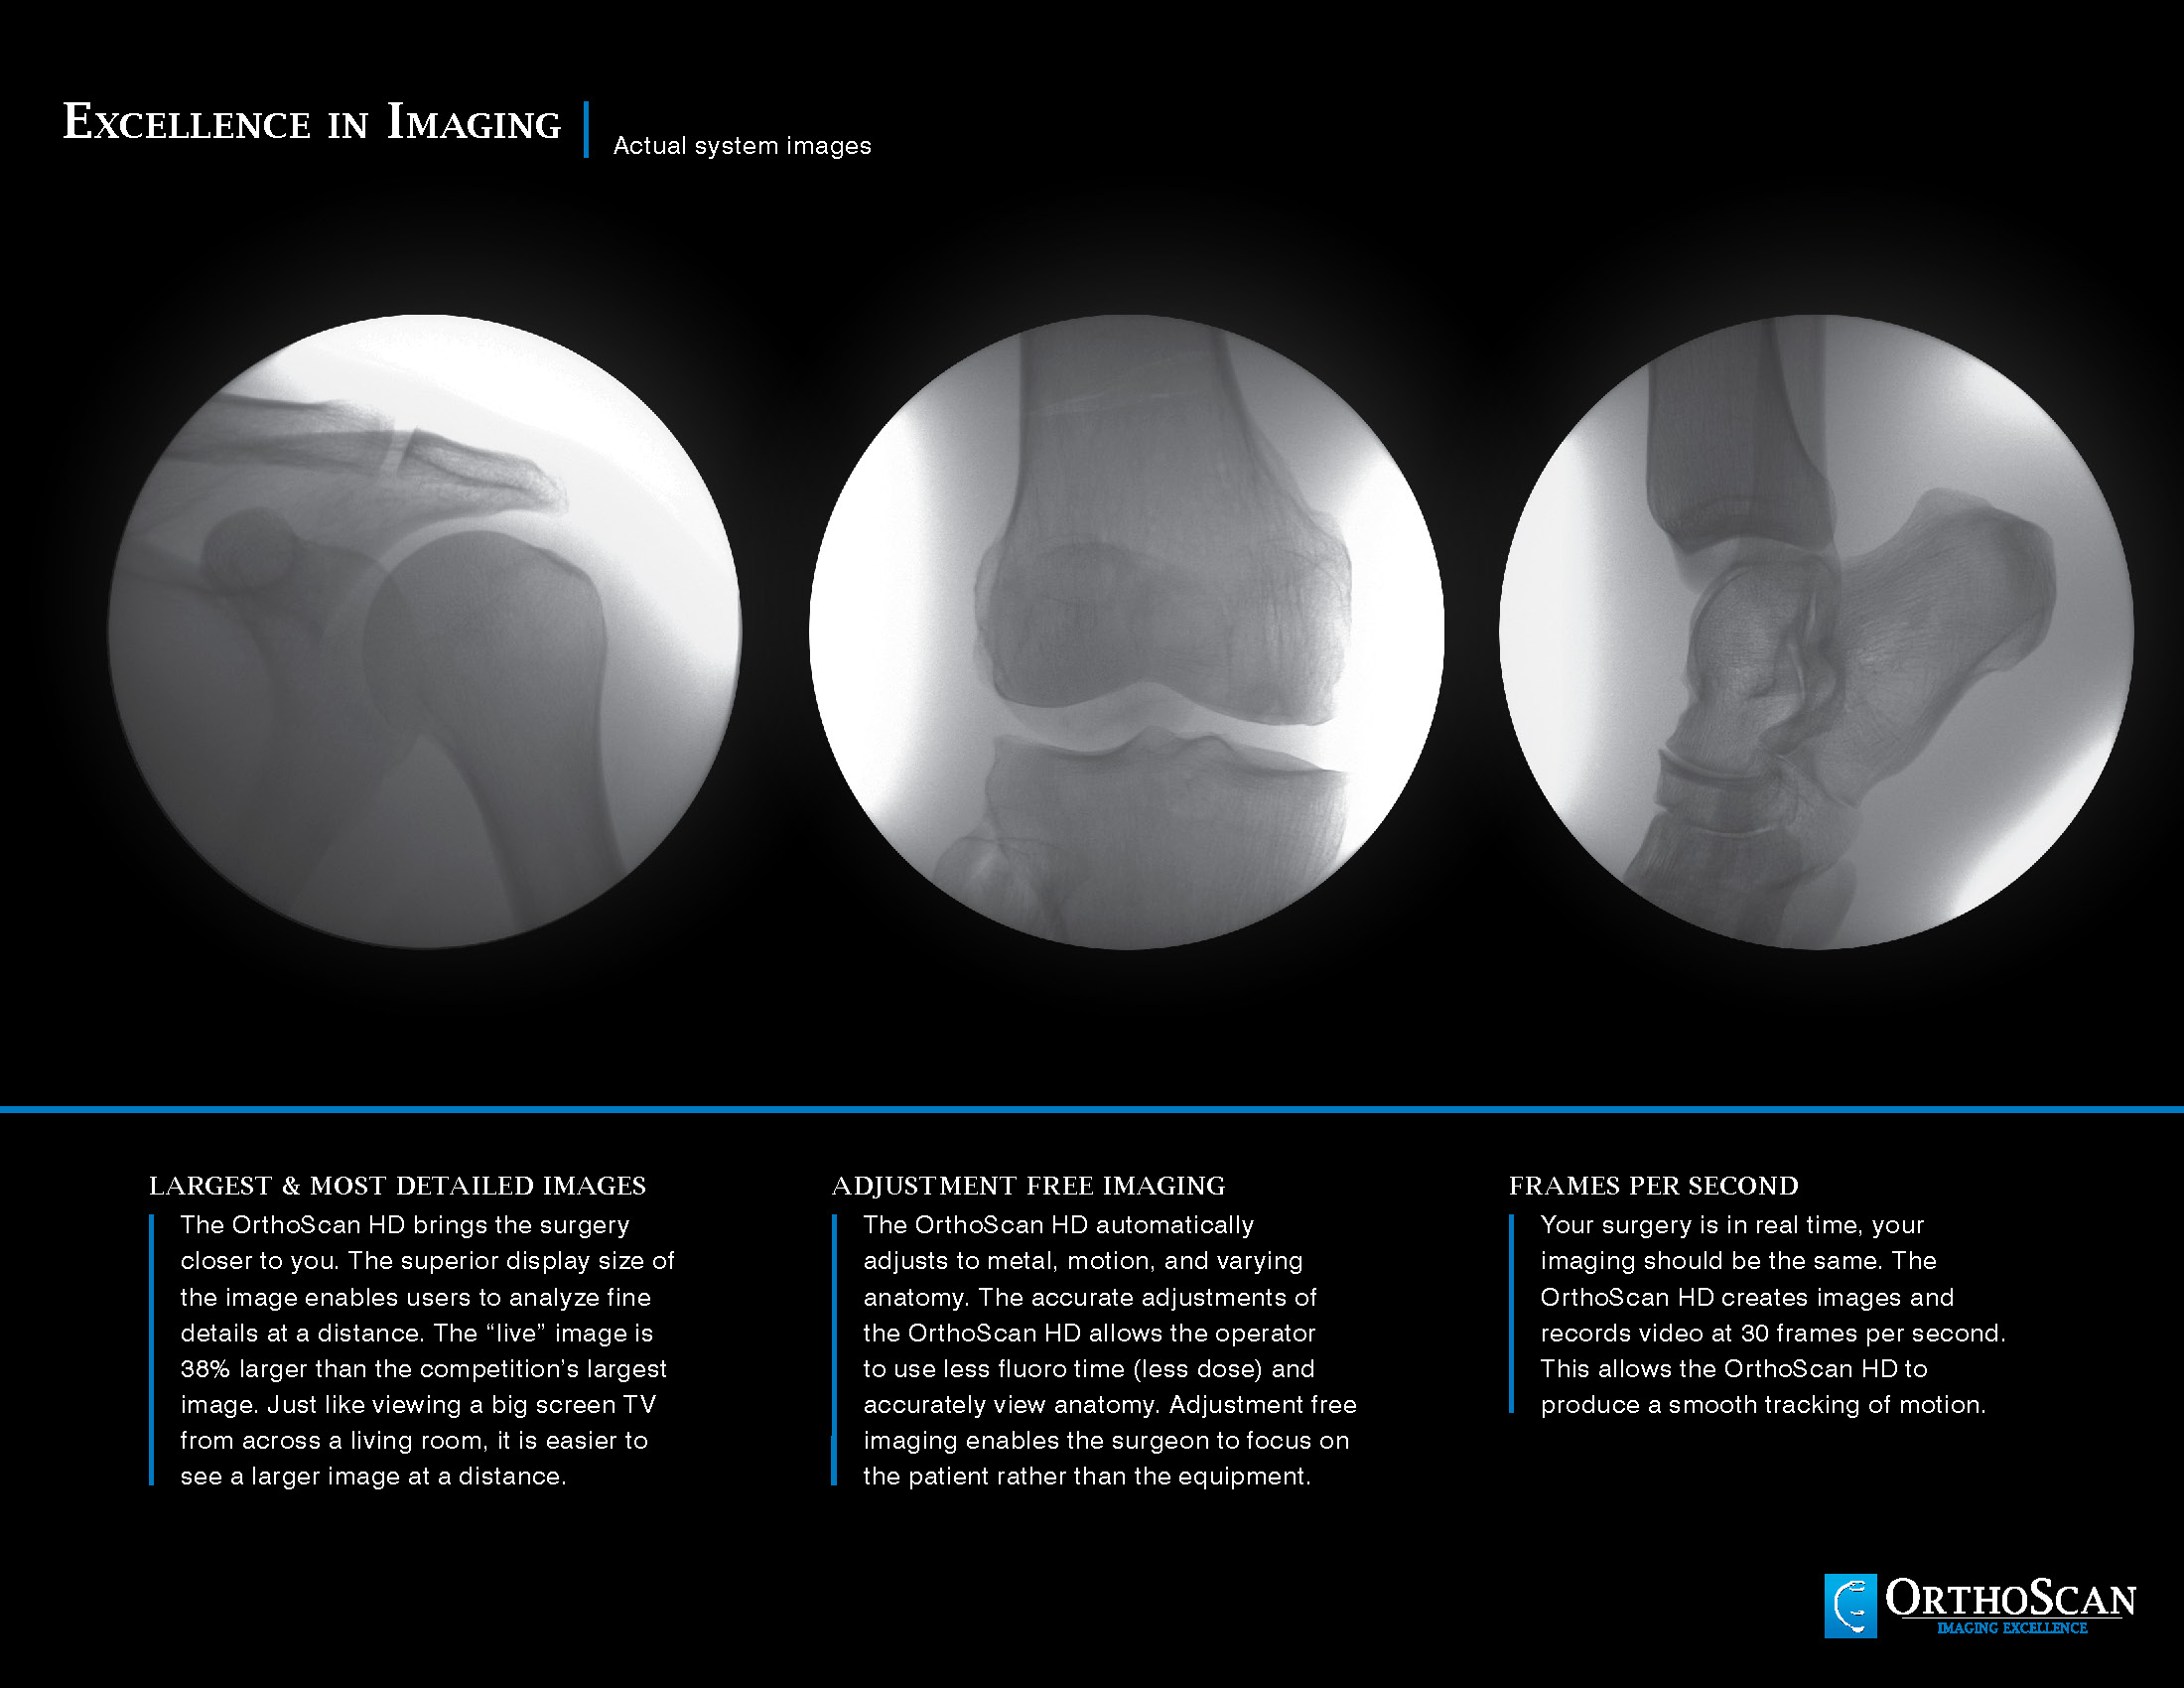

The Advanced Arthritis Relief Program (AARP) is a knee osteoarthritis (OA)  treatment system that consists of fluoroscopic guided injections of Hyaluronic Acid, targeted Physical Therapy, and a special uploading Knee Brace. It’s MD, MP, and PA approved and covered by all major insurance carriers as well as Medicare.

Precision Injections guided by using

a fluroscopy

Fluroscopy